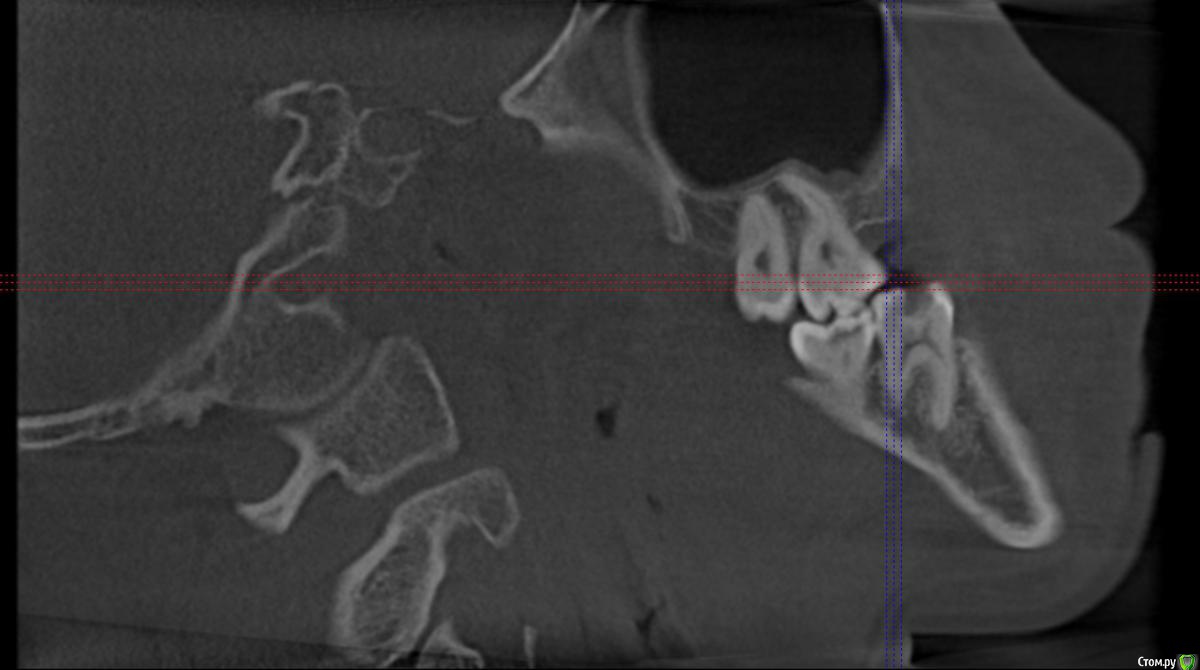

Секатор Опубликовано 4 октября, 2015 Поделиться Опубликовано 4 октября, 2015 (изменено) Здраствуйте,уже писал,но проблем много,но сча есть снимки зд(ссори за флуд).Начну издалека года два летом примерно неделю начили болеть зубы справа с отдованием в ухо и висок,оперативно ничего не делал(спас ал алкоголь),но я решил,что это 8-ки,и за зиму последнию все удалил,но отдования в висок и болезненность уха осталось,много времени прошло после удаления.Напряжение у виска и в области уха,взгляните на мою 6 справа,дно пазухи деформировано под её давлением,боли в области зуба нет-она причина?По лор все чисто,как будто болит зуб отдовая в ухо и висок,но без боли в области челюсти.Ближе к внутренней стенки пазухи и заходя на неё сформирован остроконечный конус дном пазухи,вследствии давлении корня зуба. Изменено 4 октября, 2015 пользователем Секатор 1 Ссылка на комментарий

Секатор Опубликовано 15 октября, 2015 Автор Поделиться Опубликовано 15 октября, 2015 (изменено) И,ещё раз прошу взглянуть смотрите,как деформирована внутреннеяя стенка пазухи зубом,у дна.Может корень подцепил,стенку пазухи? Изменено 15 октября, 2015 пользователем Секатор Ссылка на комментарий